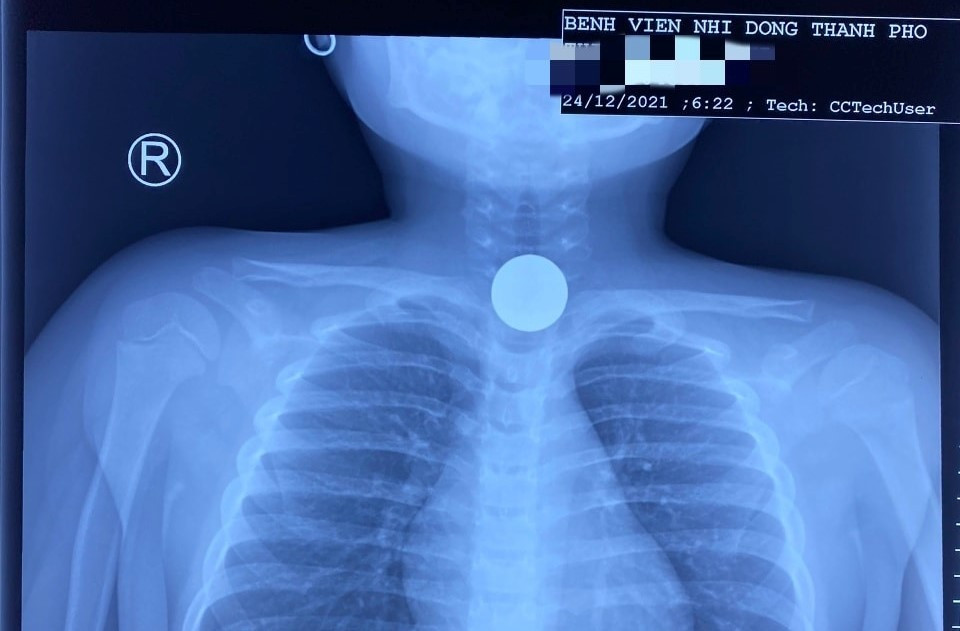

Bé 5 tuổi nuốt đồng xu, cấp cứu trong đêm giáng sinh

Khi người thân phát hiện cháu bé ói liên tục nên vội vàng đưa đến bệnh viện. Các bác sĩ đã gắp ra một đồng xu dùng để chơi game đang mắc ở thực quản.

Sau khi thăm khám, chụp X-quang ngực, đội ngũ y bác sĩ phát hiện một đồng xu ở vùng ngực đoạn D1-D2. Bệnh nhân sau đó được chuyển sang khoa Gây mê - Phẫu thuật. Tại đây, ê-kíp trực tiến hành phẫu thuật, nội soi và gắp thành công dị vật ra ngoài an toàn.